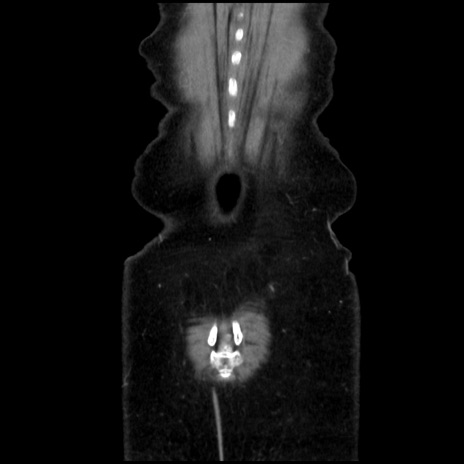

矢状断像

【症例】40歳代 女性

【主訴】上腹部痛、嘔気・嘔吐

【現病歴】約9時間前頃から急に上腹部痛、嘔気、嘔吐が出現。改善しないため救急要請。

【既往歴】子宮頚癌(広汎子宮全摘術、放射線療法)、腸閉塞

【身体所見】腹部:平坦、軟、腸雑音亢進、上腹部を中心に腹部全体に圧痛あり。

【データ】WBC 8400、CRP 0.03